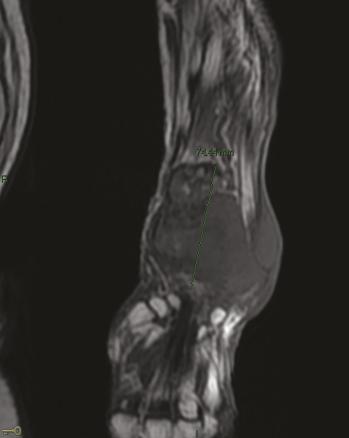

Elle est admise à l’hôpital deux ans plus tard pour des douleurs mixtes et une tuméfaction douloureuse du tiers distal de l’avant-bras gauche, dure et fixe (fig. 1 ). À l’examen physique, la patiente est grabataire et souffre de douleurs osseuses provoquées diffuses, avec une sarcopénie. La radiographie standard met en évidence une importante ostéolyse radiale inférieure, avec rupture des corticales, associée à des images d’ossifications en regard s’étendant aux parties molles épaissies (fig. 2 ). Le même aspect est confirmé sur l’IRM (fig. 3 ). La tomodensitométrie (TDM) thoraco-abdomino-pelvienne est normale. La mammographie ne retrouve pas d’anomalie. La biopsie chirurgicale montre une lésion inhabituelle associant une substance amorphe, une ostéogenèse et des cellules atypiques. Un diagnostic formel n’a pas pu être posé et il n’y avait pas d’arguments pour une origine maligne ou une tumeur osseuse primitive sur le prélèvement. Par ailleurs, le bilan de fractures multiples n’a pas mis en évidence de syndrome inflammatoire biologique. En revanche, une hypophosphorémie a motivé la réalisation d’une scintigraphie osseuse montrant un aspect évocateur d’ostéomalacie.